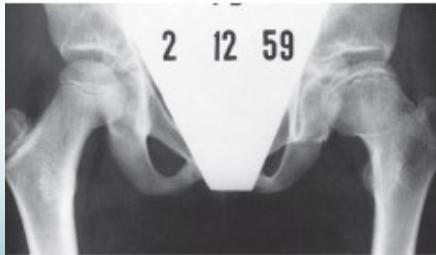

Radiographic Stages:

-

Initial/ Bone Death Stage - May initially appear normal on x-ray

- Increased density followed by collapse

Revascularization and Repair Stage - Reduced density and fragmentation on x-ray

Distortion and Remodeling Stage - Distortion, flattening (coxa plana)

- Enlargement (coxa magna) with partial uncoverage

Radiological Progression:

Progression: Sclerosis → Collapse → Fragmentation → Remodeling

Imaging Examples: